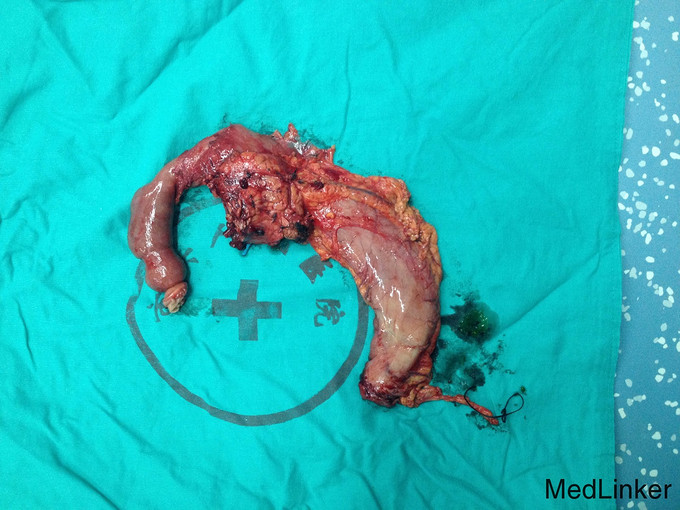

治疗经过:患者入院后于无明显诱因下出现右上腹疼痛,压痛明显,拒按。结合腹部CT及MRI影像学表现,胰胆管明显扩张,考虑急性胰腺炎发作。辅查:淀粉酶(干式) 1640 U/L ↑。总蛋白 61 g/L ,白蛋白 36 g/L ,白/球比例 1.4 ,谷丙转氨酶 218 U/L ↑,谷草转氨酶 183 U/L ↑,γ-谷氨酰酶 548 U/L ↑,总胆红素 13.3 μmol/L ,直接胆红素 5.4 μmol/L ,肌酐 66 μmol/L ,血清钾 4.3 mmol/L ,血清钠 142 mmol/L ,血清氯 106 mmol/L ↑。白细胞 6.3 *10^9/L ,红细胞 3.84 X10^12/L ,血红蛋白 117 g/L ,细胞比积 35.9 % ,血小板 197 X10^9/L ,中性细胞百分比 58.7 % 。甲胎蛋白(AFP) 2.68 ng/mL ,癌胚抗原(CEA) 4.99 ng/mL ,糖类抗原(CA125) 6.91 U/mL ,糖类抗原(CA199) 39.45 U/mL ↑。处理:予禁食,查血、尿淀粉酶,抑酸、保肝、补液支持治疗,经治疗后症状缓解。后因患者无黄疸,为进一步明确胆总管梗阻原因,行ERCP+ERBD+十二指肠乳头活检术。 检查治疗经过:十二指肠镜进入十二指肠,降部内侧见乳头,十二指肠乳头肿大,粘膜面外观正常,触之易出血。BOSTON-Jagwire导丝留置胰管,BOSTON-Jagwire导丝进入胆管引导COOK-FS-OMNI导管造影,胆管显影,胆管扩张,胰管造影胰管扩张。胆管胰管内未见充盈缺损。十二指肠乳头开口处取四块活检。放置辛菖猪胆道引流管(8.5F,6cm),辛菖胰管引流(F5,4cm),引流畅。结合MRI及CT考虑壶腹部占位可能。 十二指肠乳头活检病理:绒毛状腺瘤伴部分腺体重度不典型增生,局灶癌变。 患者术前诊断为十二指肠壶腹部癌,行剖腹探查,胰十二指肠切除术。术中见:见腹腔内无腹水,腹膜、盆腔内、大网膜、肝脏、肝十二指肠韧带、胰腺周围、腹腔动脉周围、肠系膜根部、腹主动脉旁等无转移性结节和肿大淋巴结。探查见此患者左右肝胆管的汇合处接近胆胰管汇合处,右侧肝胆管壁水肿增粗,十二指肠乳头部肿块大小0.3cm,行胰十二指肠完整切除。 术后病理检查报告:下半胃、胰腺、十二指肠;标本类型:切除胰腺大小 4×4×1 CM,十二指肠长 15CM,胃小弯长 8 CM,大弯长 11CM,胆囊9×3×1.5CM;肿瘤部位:肿瘤位于十二指肠乳头,大小0.5×0.3CM;组织学类型内容: 腺癌II级;血管浸润(-),淋巴管浸润(-),神经周围浸润(-);切缘: 上、下切缘及胰腺切缘均未见癌;淋巴结:以下淋巴结均未见癌转移:胰腺旁LN:0/8枚,胃大弯LN:0/6枚,胃小弯LN:0/3枚。;淋巴结免疫反应状态: SH(+), PH(+), GH(+);肿瘤旁病变: 粘膜组织慢性炎(十二指肠乳头):腺癌II级,肿瘤侵及肌层,未累及胰腺,胰腺导管扩张,小胆管增生伴中度不典型增生。(胆囊):慢性胆囊炎伴腺体增生。肿瘤组织免疫酶标记结果:CA199(-)、CEA(+)、S-100(-)、CK19(+)、CK7(+)、CDX2(-)、CK(-)、Ki67(80%+)。